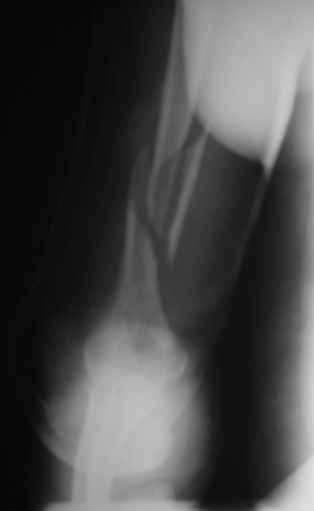

Теперь непосредственно по больному. Лечим функциональной повязкой, добились вот чего (приложение). Будем признательны за дальнейший комментарий - мое мнение, что можно продолжить без операции.

Юрий Алексеевич Булахтин